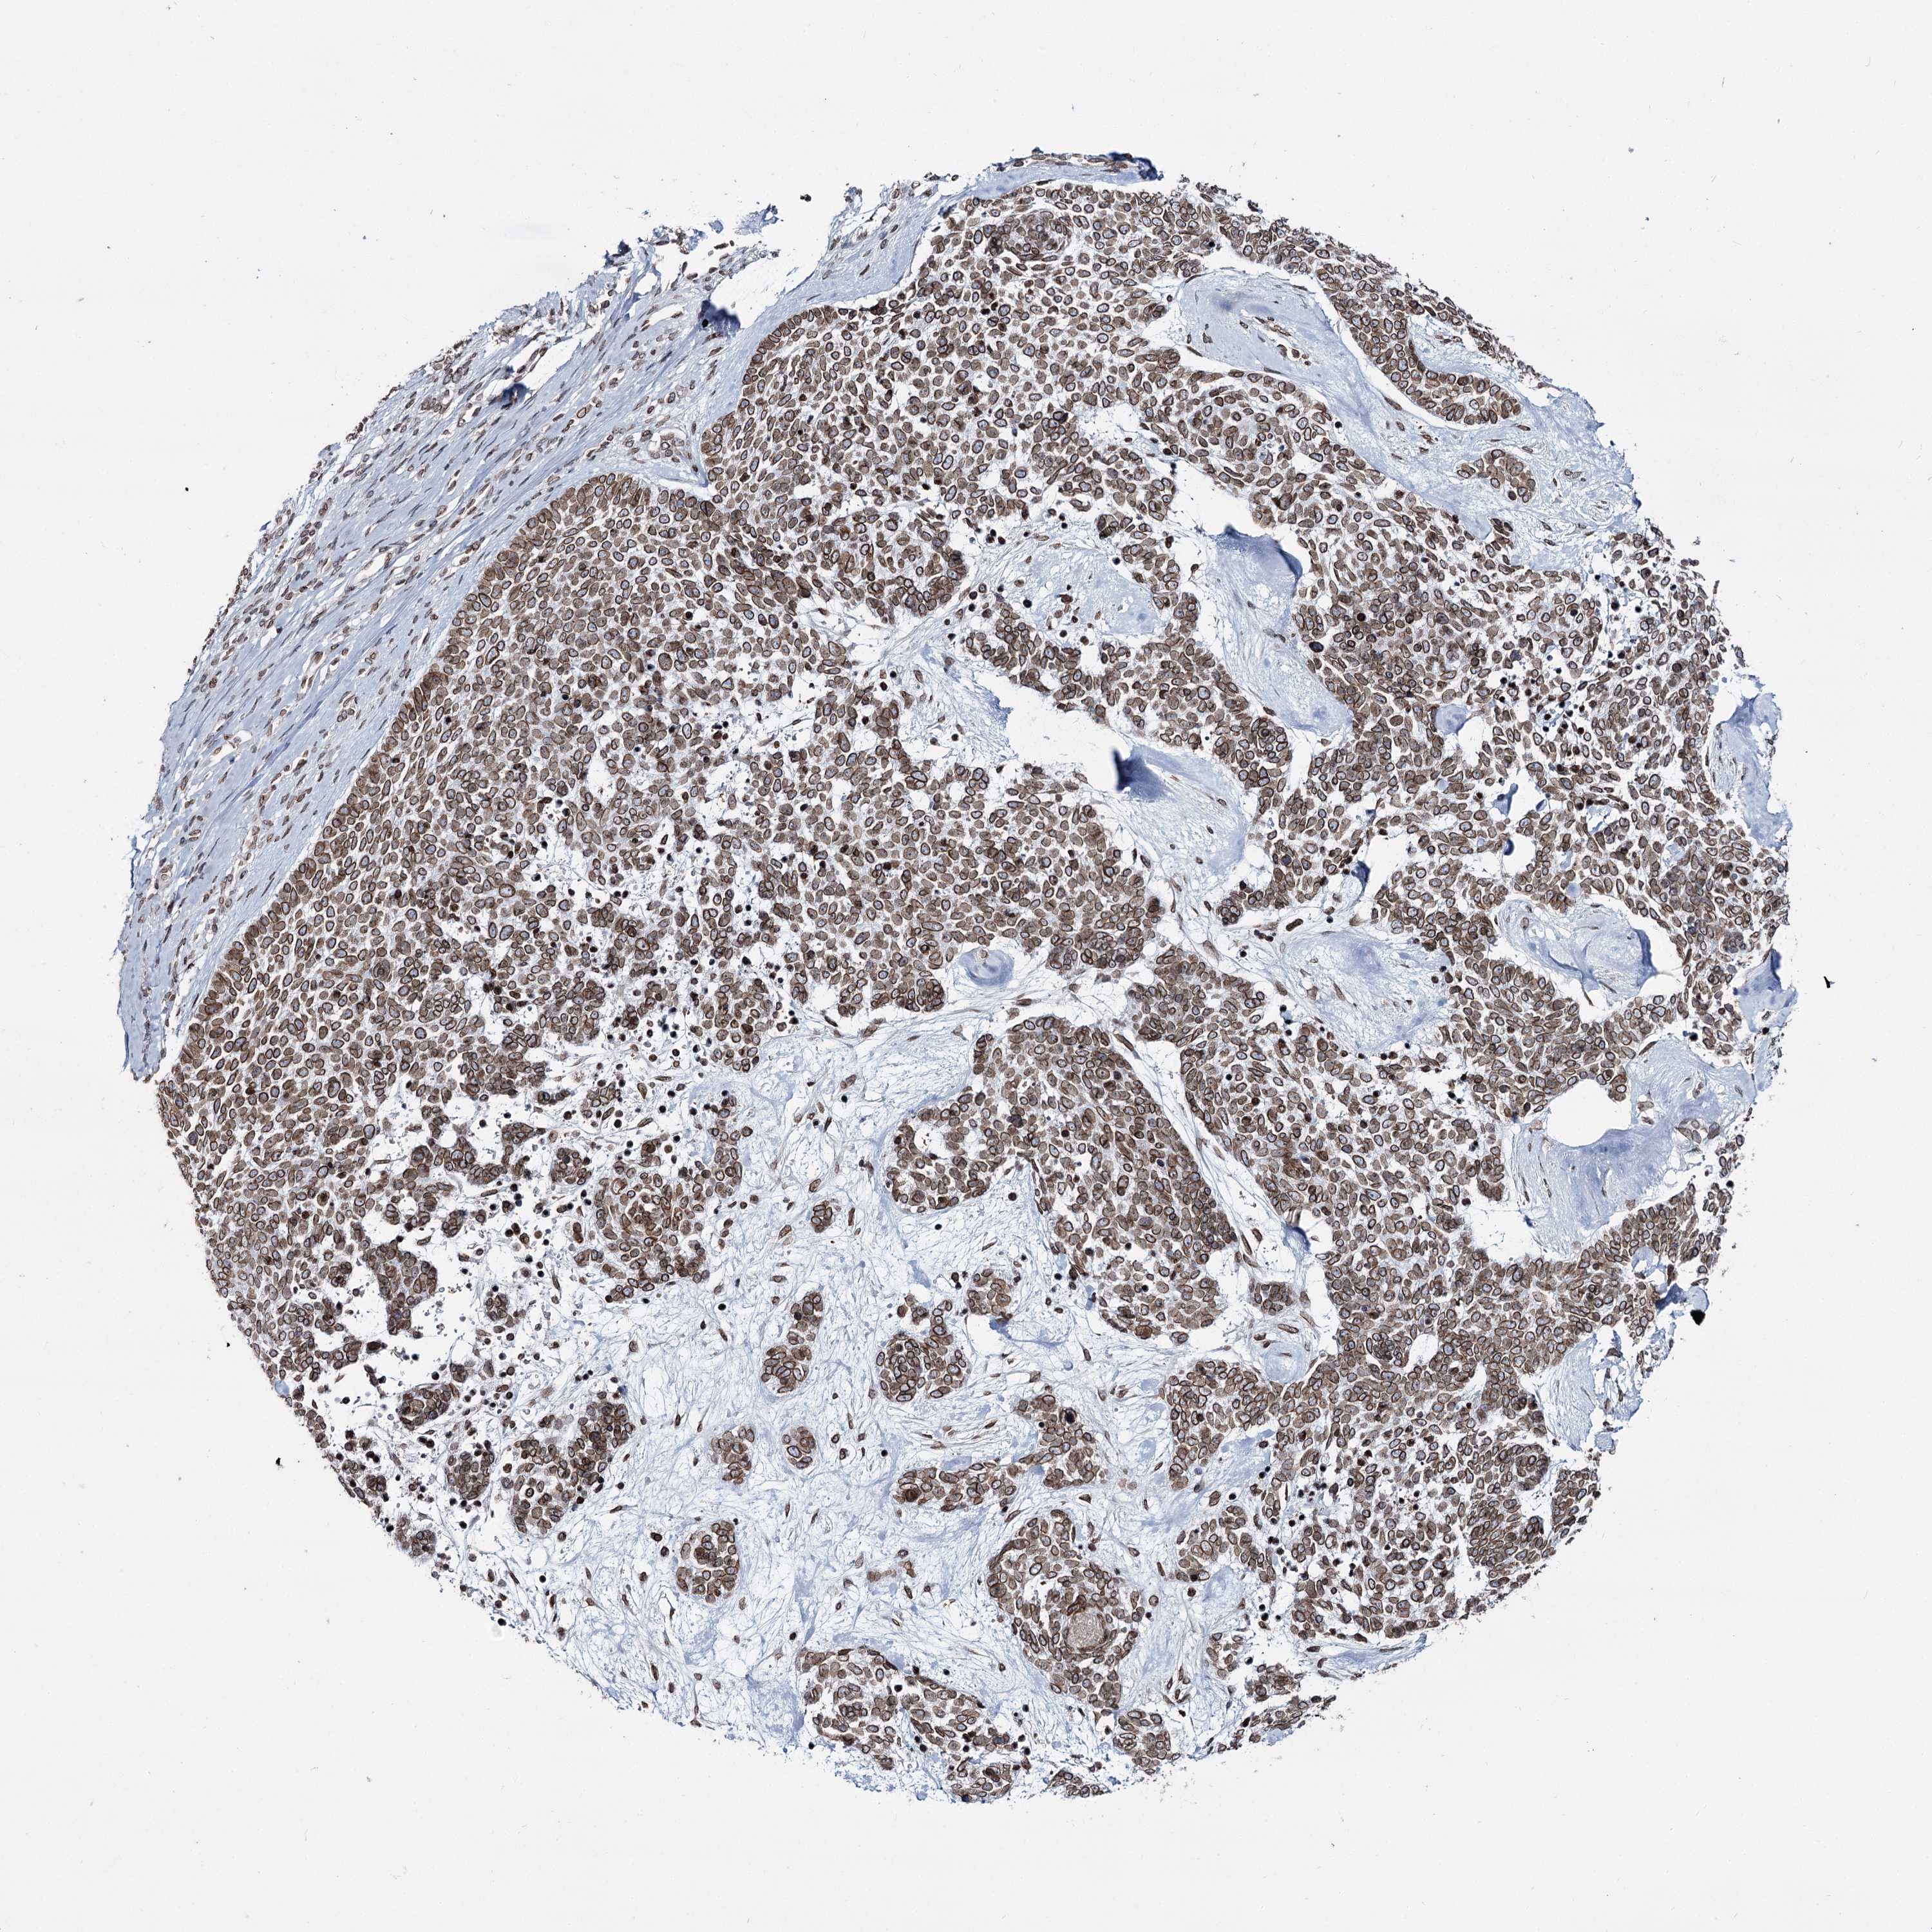

SKIN CANCER - Protein expressioni

A mouse-over function shows sample information and annotation data. Click on an image to view it in a full screen mode. Samples can be filtered based on level of antibody staining by selecting one or several of the following categories: high, medium, low and not detected. The assay and annotation is described here.

Antibody stainingi

Antibody staining in the annotated cell types in the current human tissue is reported as not detected, low, medium, or high, based on conventional immunohistochemistry profiling in selected tissues. This score is based on the combination of the staining intensity and fraction of stained cells.

Each image is clickable and will lead to virtual microscopy that enables deeper exploration of all samples and also displays staining intensity scores, fraction scores and subcellular localization as well as patient and tissue information for each sample.

Antibody HPA038091

Staining

High

Intensity

Strong

Quantity

>75%

Location

Nuclear

Basal cell carcinoma